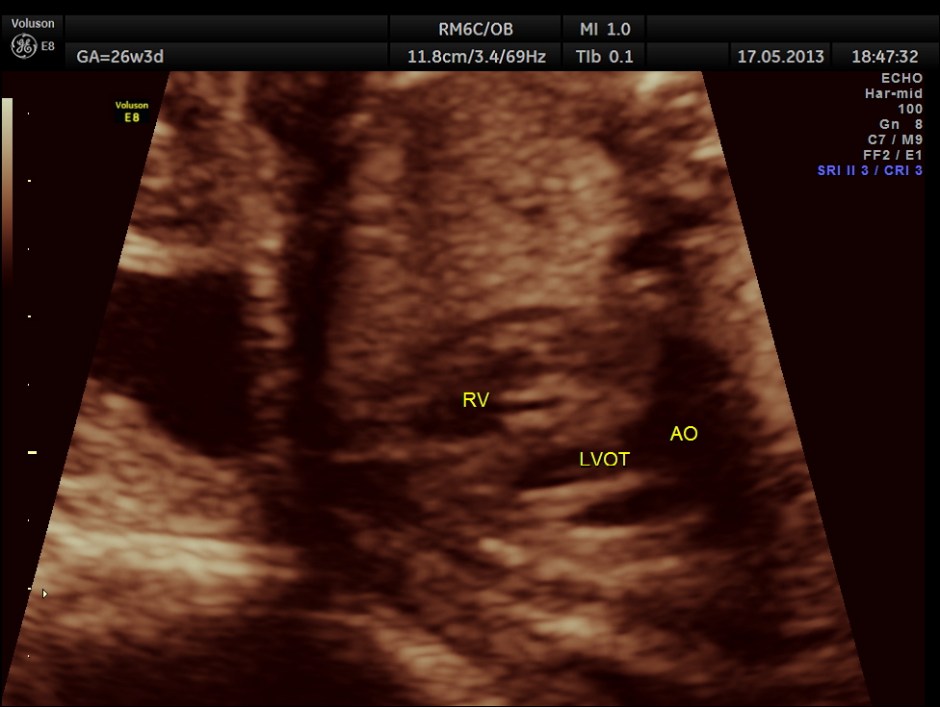

The following images show the sections of the heart.

This fetus did not show any oro-facial clefts ; heart and spine appeared normal.